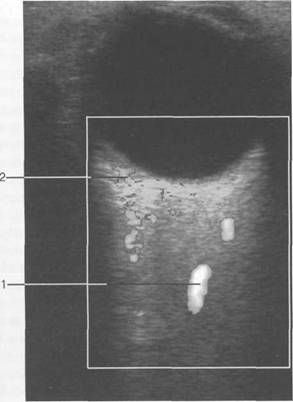

орбитальная клетчатка 4 3

(corpus adiposum orbitale).

HU), каплив 121h711b ают контрастный препарат. Толщина хнюю прямую мышцу видно плохо, обычно ее изображение слив 121h711b ается с изображением мыш­